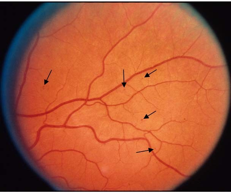

视网膜内微血管异常(IRMA)

视网膜内微血管异常(IRMA)是扭曲扩展的视网膜内血管片段。

视网膜上的点状微血管瘤和视网膜表面清晰可见的新生血管都不属于视网膜内微血管异常。

▲ 视网膜内微血管异常(A)

▲ 视网膜内微血管异常(B)